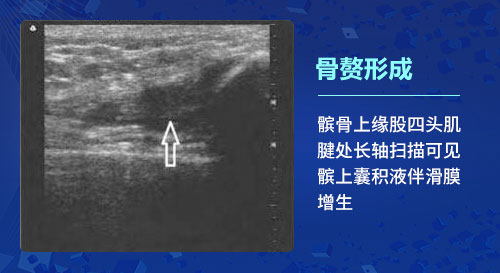

二、骨贅形成:隨著骨關(guān)節(jié)炎的病情進(jìn)展,骨關(guān)節(jié)炎患者的軟骨退變通常軟骨內(nèi)會(huì)伴隨骨化形成的骨贅,如果骨贅比較大,則可能影響骨關(guān)節(jié)的正�;顒�(dòng),甚至脫落在髕上囊或關(guān)節(jié)腔內(nèi)而導(dǎo)致游離體形成。關(guān)節(jié)病變還會(huì)刺激鄰近組織和滑膜,導(dǎo)致滑膜增生及炎性滲出。肌骨超聲技術(shù)可觀測(cè)到關(guān)節(jié)邊緣出現(xiàn)不規(guī)則的強(qiáng)回聲突出,判斷患者病變部位是否存在滑膜肥大、增生,越是嚴(yán)重的滑膜增厚,顯示出彩色的血流信號(hào)也就會(huì)越豐富。